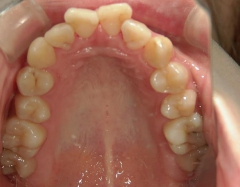

矯正歯科 治療前

矯正_灰色.pngno.6_8296_治療前_上.jpg矯正_灰色.png